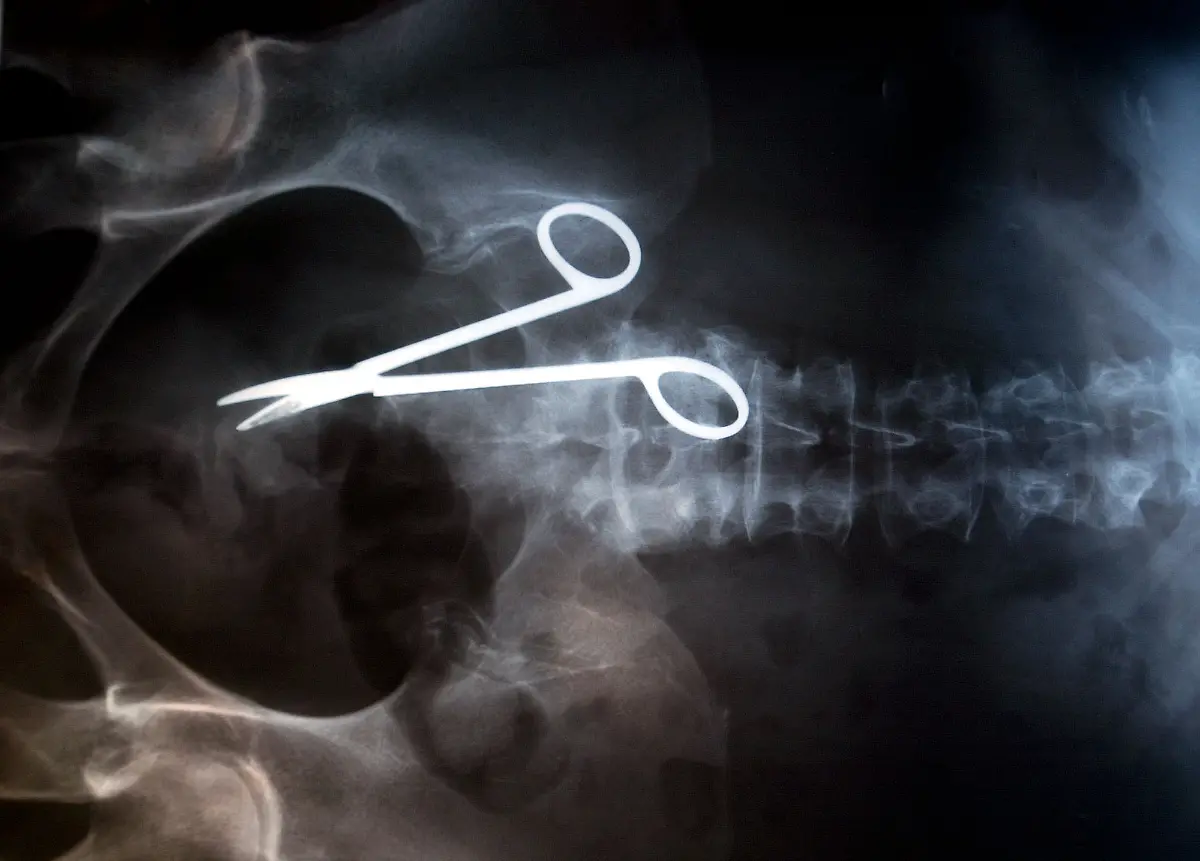

Nägel, Messer, TelefoneWas Röntgenstrahlen zum Vorschein bringen

Nicht immer zeigen Röntgenaufnahmen das, was man von ihnen erwartet. Oft kommt es zu Bildern, die selbst hartgesottene Betrachter zum Schaudern bringen - und der Wissenschaft Rätsel aufgeben.